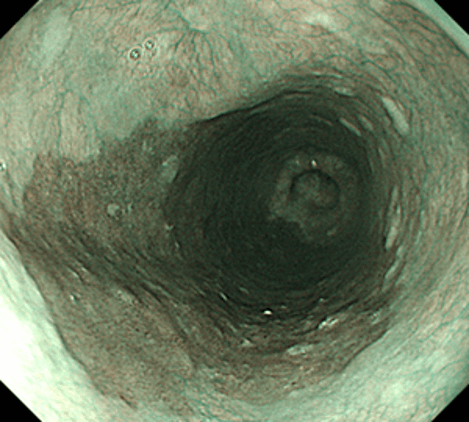

食道の粘膜の表面は、胃や大腸の粘膜表層を構成する腺上皮とは異なり、皮膚・口腔・肛門管と同様の重層扁平上皮で覆われています。その食道粘膜表層の重層扁平上皮ががん化することで発生する悪性腫瘍が、典型的な食道がんとされている扁平上皮がんです。本邦の食道がんの9割弱は扁平上皮がんであるとされています(残りのほとんどはバレット腺がん)。早期の食道がんや表在型食道がんにおいては症状がほとんどないため、内視鏡検査によってたまたま見つかることがある一方で、発見が遅れて進行してから見つかるケースも少なくありません。

食道がん(扁平上皮がん)